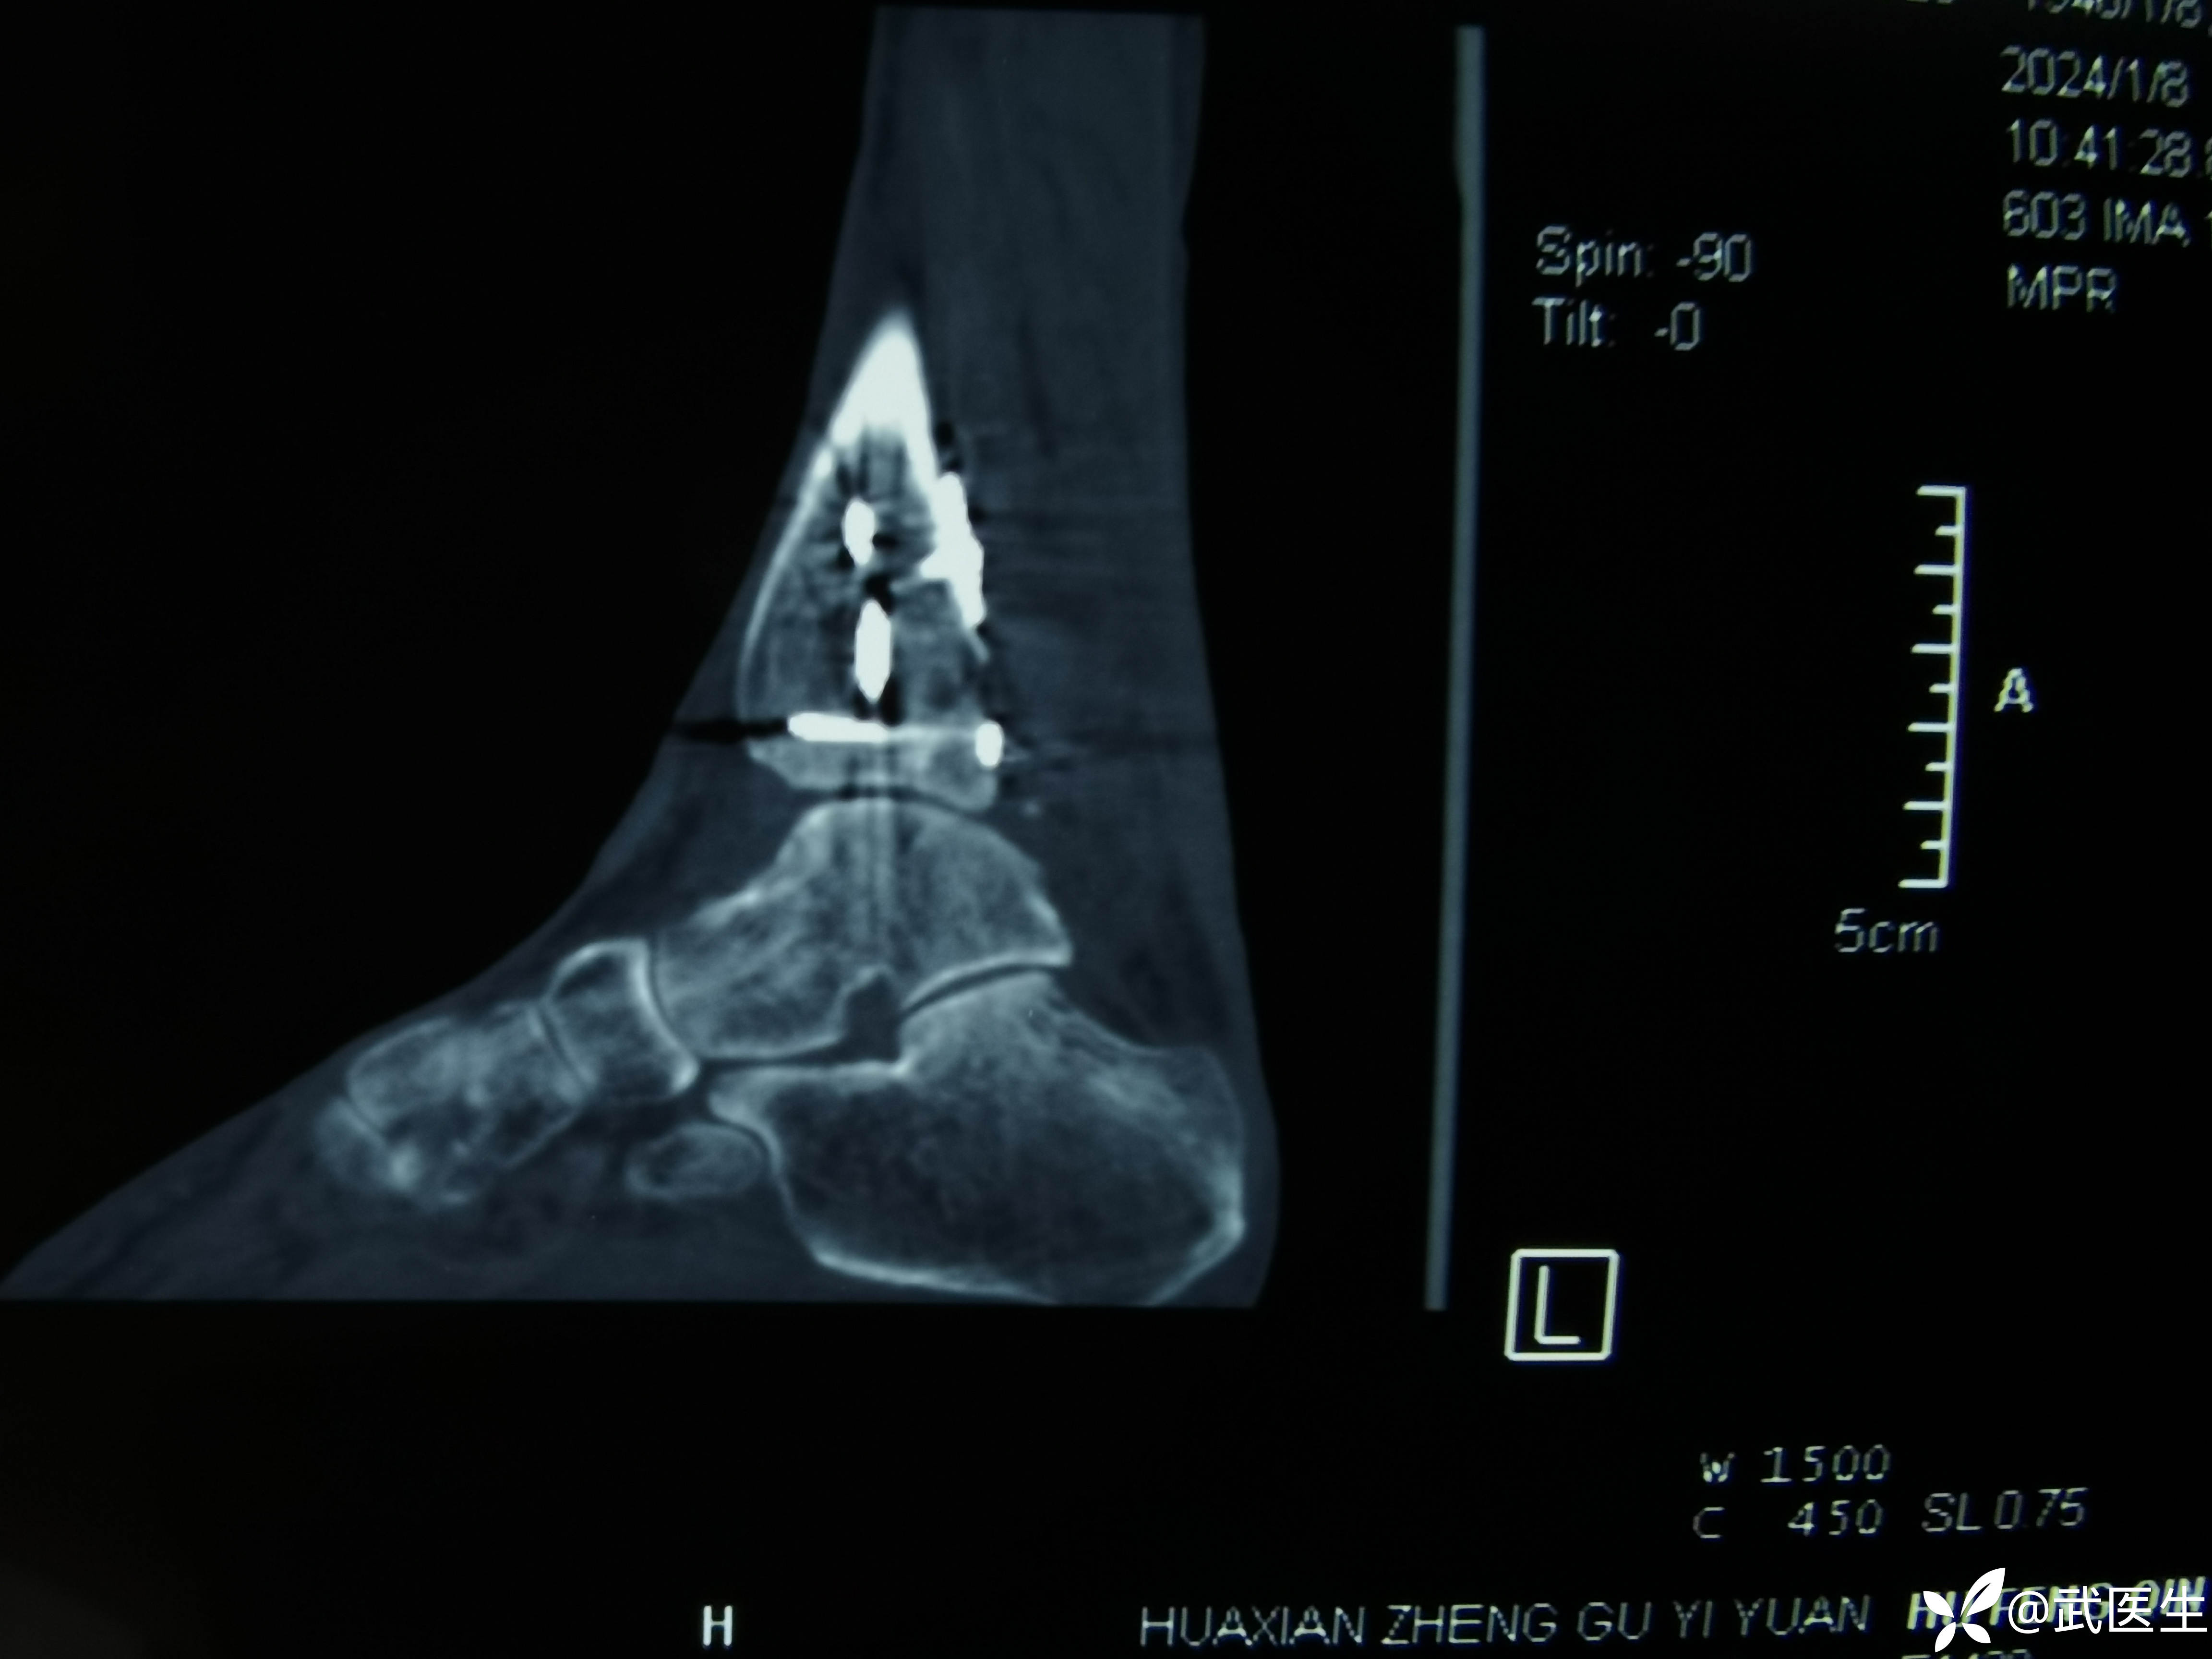

术后ct,复位还行